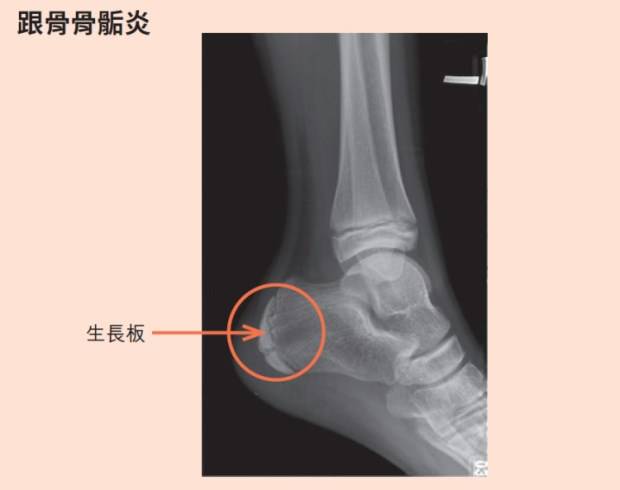

孩子常喊腳很痛 足踝外科醫師 別把孩子的莫名腳痛開心當成是 轉大人的生長痛 Vidaorange

家有學齡兒童注意 腳跟痛就是 轉大人 骨科醫師提醒 別把 骨骺炎 當生長痛 良醫健康網 Line Today

以為只是扭到腳竟骨折傷到生長板 骨科 復健 科別 元氣網